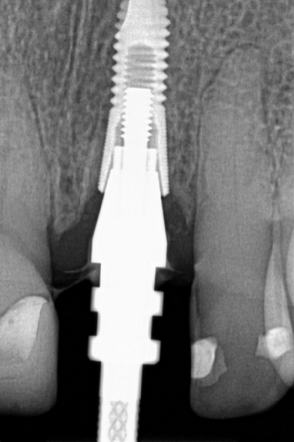

Following the recommendations of Yi, the transmucosal portion of the prosthetic connections should be flat or concave in profile diverging no more that 30 degrees from the long axis of the implants.19 Standard abutment profiles which are flat or convex in profiles are good examples to follow (Figure 19). Following Yi's recommendations individual posterior custom abutments with narrow implants should have flat or concave transmucosal profiles like a standard implant abutment with convex intaglio shapes like pontics that are cleanable with dental floss19 (Figure 20 through Figure 28).

(19.) Standard implant abutments.

Figure 19

(20.)  Molar custom abutment.

Figure 20